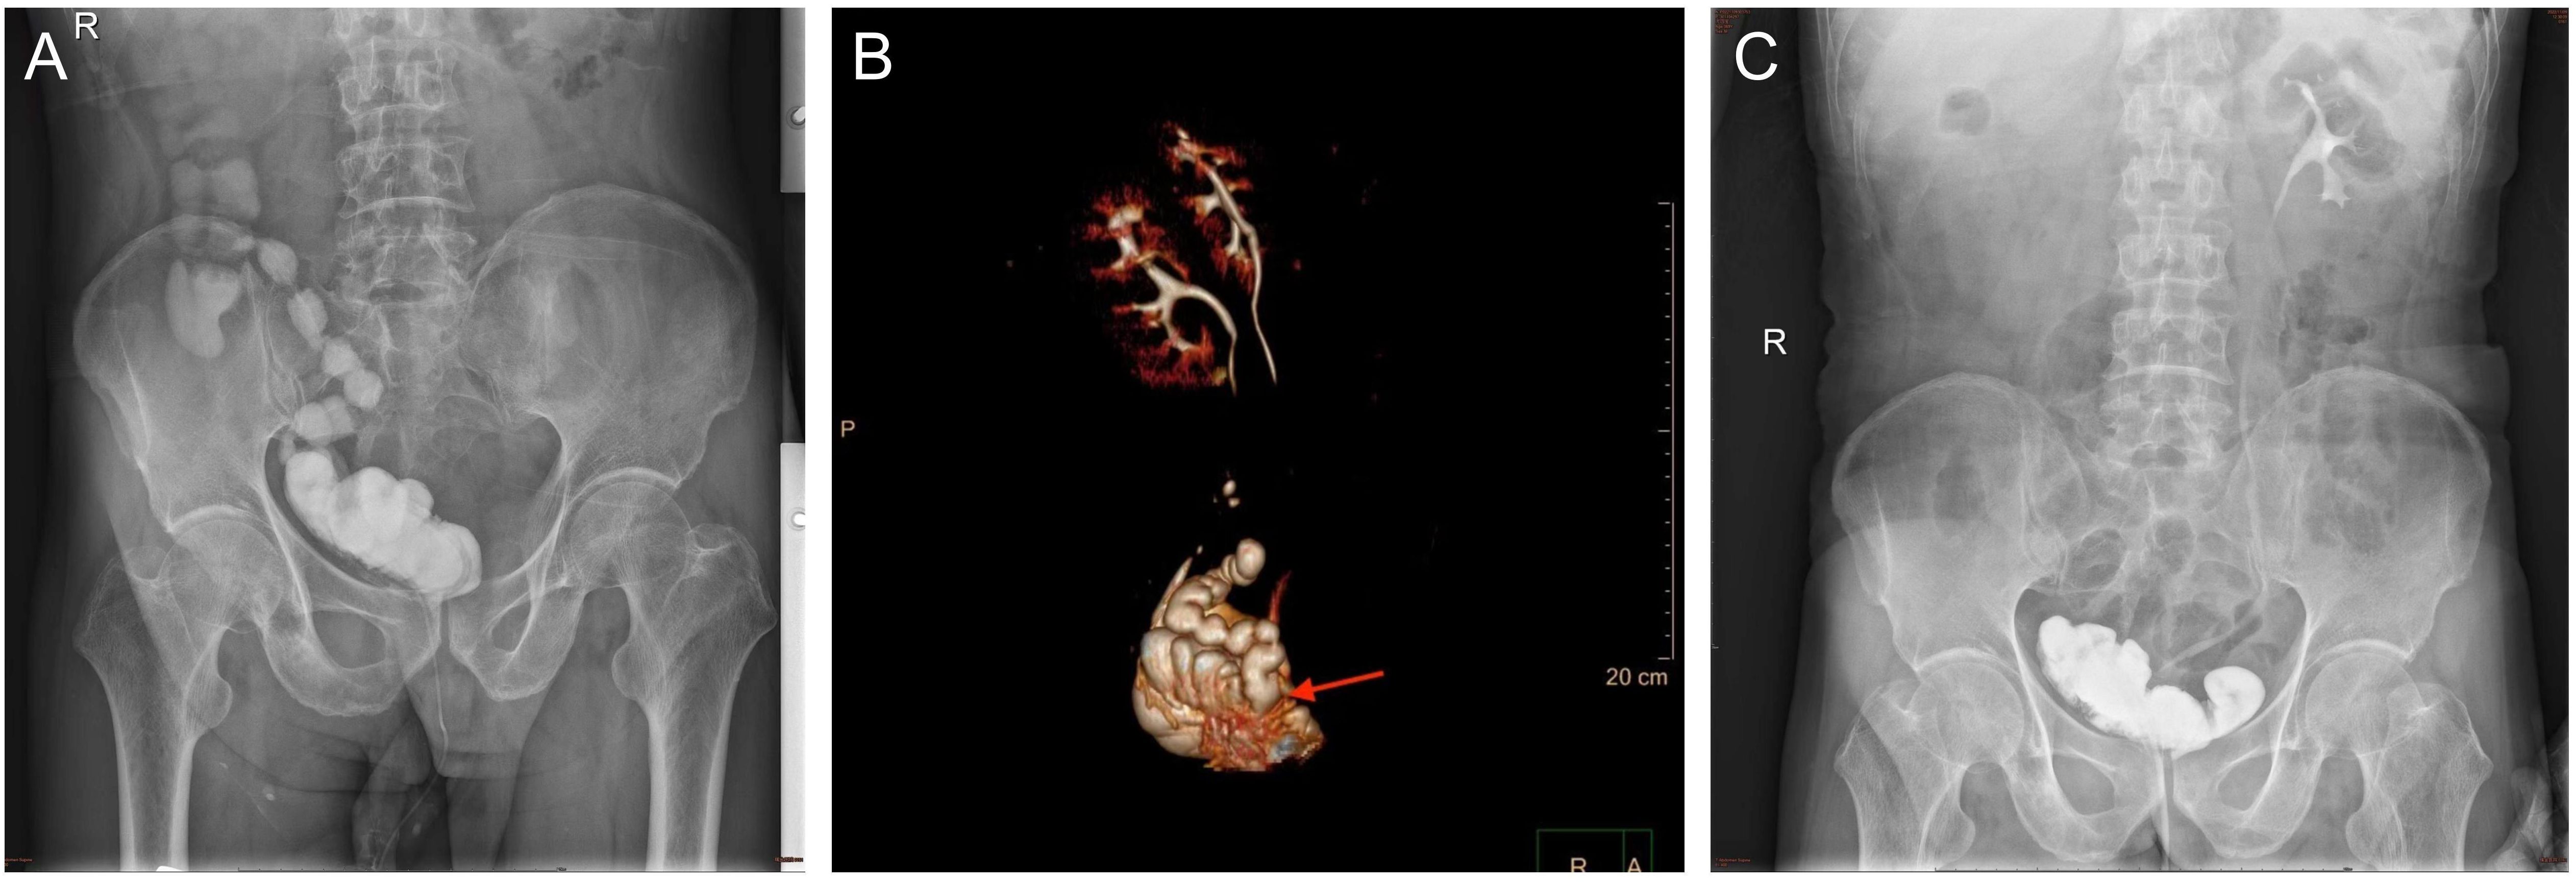

One month after surgery, the patient returned to the outpatient clinic because of the presence of fecal material in his urine. Cystography revealed that the contrast agent was present in the bladder, ileum, and right colon. Computed tomography urography (CTU) was performed, which explicitly lead to the suspicion of INF associated with ONB (Figures 1A, B). In patients with frequent tract infections, we scheduled an elective fistula repair operation. First, we performed proximal ileostomy on 21 March 2022 to prevent continuous fecaluria and ensure an aseptic environment in the neobladder. Fecaluria did not occur immediately after ileostomy, further confirming our hypothesis of INF.

Figure 1. (A) The image of cystography examination showed the contrast agent was found in the ileum and right colon before the surgery. (B) Computed tomography urography reconstructed the spatial position of the neobladder and ileum. (C) The image of cystography examination showed the contrast agent was not found in the ileum and right colon after the surgery.

Postoperative recovery was good, and the patient was discharged seven days after the surgery. Twenty days later, cystography revealed that the contrast agent was not present outside the neobladder (Figure 1C). The patient has been regularly followed-up. The patient did not experience fecaluria or digestive discomfort. The daytime and nighttime urinary continence rates were 100% and 75%, respectively. A timeline illustrating the information in this case is presented in Figure 3.